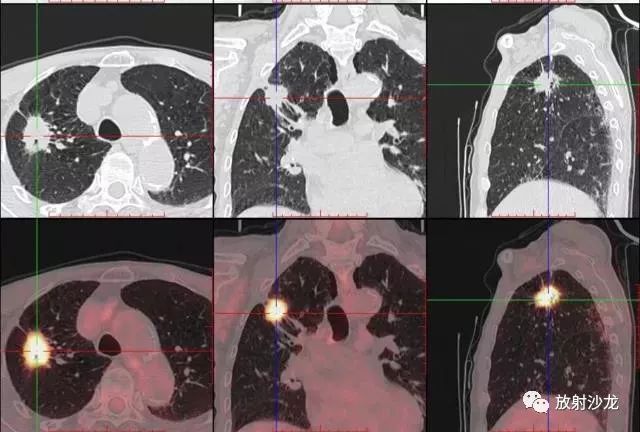

PET-CT是目前世界上最先進(jìn)的核醫(yī)學(xué)分子影像設(shè)備,中文稱為正電子發(fā)射計算機(jī)斷層/X 線計算機(jī)體層成像。

PET-CT等于PET+CT,包含PET(功能分子影像)與CT(解剖影像)的最優(yōu)化組合;即同時具有PET和CT的功能,但它絕不是二者功能的簡單疊加,因為PET與CT優(yōu)勢互補(bǔ),“1+1>2”。PET-CT除了具備PET和CT各自的功能外,其獨(dú)有的融合圖像,將PET圖像與CT圖像融合, 可以同時反映病灶的代謝,可以早期診斷疾病的同時,明顯提高診斷的準(zhǔn)確性。

18F-FDG(氟脫氧葡萄糖)是葡萄糖的類似物,是臨床最常用的顯像劑;18F-FDG能反映體內(nèi)葡萄糖利用狀況。腫瘤細(xì)胞內(nèi)可積聚大量18F-FDG,但是18F-FDG僅僅是葡萄糖類似物,腫瘤細(xì)胞攝取后不能進(jìn)一步代謝,屬于“只進(jìn)不拉”,能在腫瘤細(xì)胞內(nèi)積聚,經(jīng)PET-CT顯像可顯示腫瘤的部位、形態(tài)、大小、數(shù)量及腫瘤內(nèi)的放射性分布。同時腫瘤細(xì)胞的原發(fā)灶和轉(zhuǎn)移灶具有相似的代謝特性,一次注射18F-FDG就能方便地進(jìn)行全身顯像,18F-FDG PET-CT全身顯像對于了解腫瘤的全身累及范圍具有獨(dú)特價值。